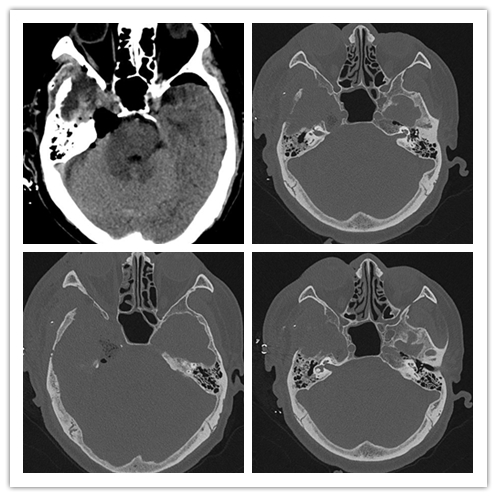

辅查:颅脑MRI:右侧CPA-中颅底占位,考虑良性肿瘤。头颅CT提示:中颅窝右份混杂密度病变,部分骨质缺损,考虑畸胎瘤、脂肪瘤等。

诊断: 1、右侧海绵窦内卵圆孔-破裂孔区脂肪瘤?